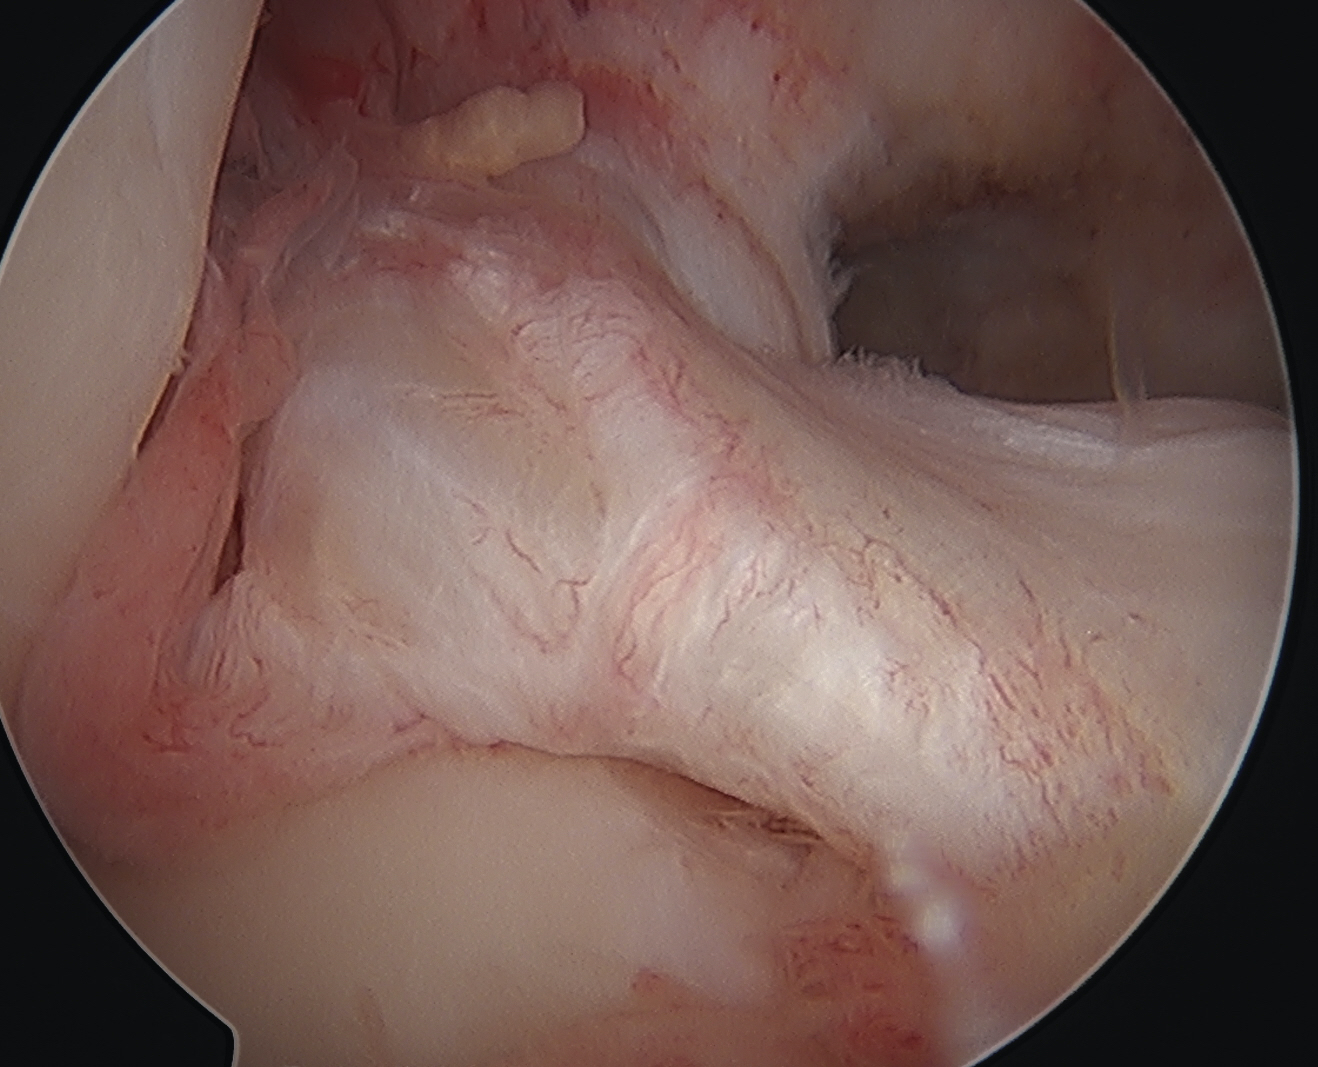

Arthroscopy

May miss tear as is extra-synovial

Chronic PCL tear from femur

Acute PCL femoral avulsion

Apparent ACL laxity due to PCL tear and posterior tibial sag; ACL tension restored with anterior drawer